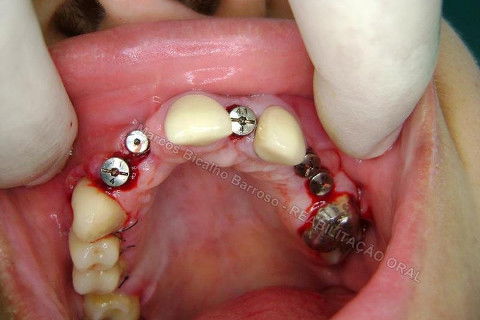

Iniciei esta etapa com o uso de um bisturi circular para contra ângulo. Na verdade, estou postando novamente este procedimento, mas realmente, cheguei depois a conclusão que não deveria ter agido assim nos dentes anteriores, onde a estética é primordial, não devemos remover tecido mole, mas manipular para promover um aumento de papila. Este bisturi é útil para dentes posteriores, adianta bastante o trabalho, é rápido, remove uma porção do formato e dimensão da plataforma do implante, a conta para adaptação do cicatrizador.

Reparem no corte...bonitinho mas fiquei com raiva depois. rsrsrs. Caramba, por que que eu tinha que tirar esta gengiva dali? Era só enrolar o excesso para a vestibular e conseguiria um bom aumento de volume gengival, o que ajudaria bastante na estética periimplantar. Mas tudo bem, vou fazer a cirurgia periodontal depois para corrigir isto sem cobrar da paciente, só de raiva. hehehe. Tem que rir para não chorar.

Aqui até que tudo bem, mas nos anteriores, não podia.